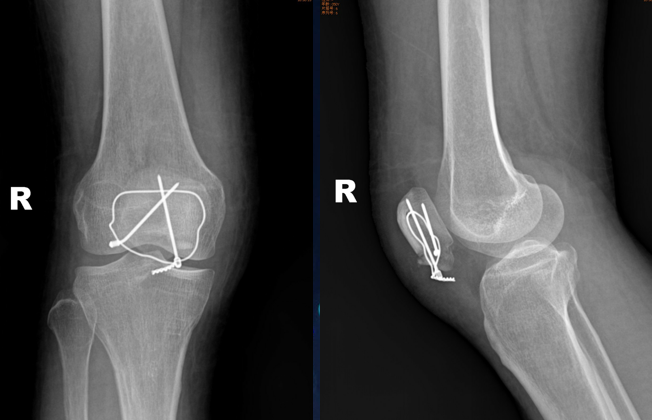

主诉:摔伤致右膝部肿痛,活动受限。

查体:右膝部肿胀,压痛,活动受限明显。下肢血运感觉正常,各趾可自主活动。

辅助检查:X片示右髌骨骨折,骨折端分离

诊断:右髌骨骨折(下极骨折)

术后复查